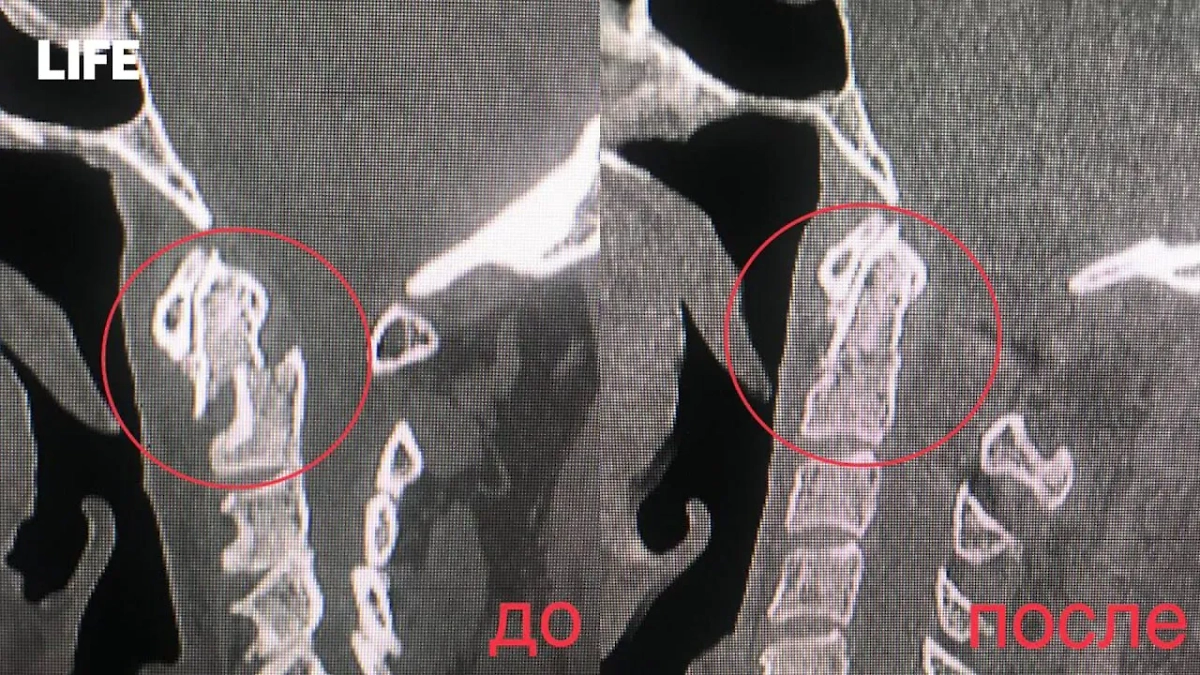

В Видновскую клиническую больницу скорая доставила 64-летнего мужчину с серьёзным повреждением шеи, рассказали Life.ru в медучреждении. Дома он неудачно поскользнулся, после чего его состояние резко ухудшилось: кружилась голова, сознание путалось, реакции затормаживались, руки и ноги слабели и немели. Обследование показало нестабильный перелом второго позвонка с осколками, смещением и сжатием спинного мозга.

Хирургам пришлось филигранно вправить смещённые позвонки, зафиксировав их винтами с двух сторон, а заодно провести ламинэктомию первого позвонка — убрать его часть, чтобы освободить спинной мозг от давления. Операция на шейном отделе, по словам врачей, — это ювелирная работа, где нет права на ошибку.